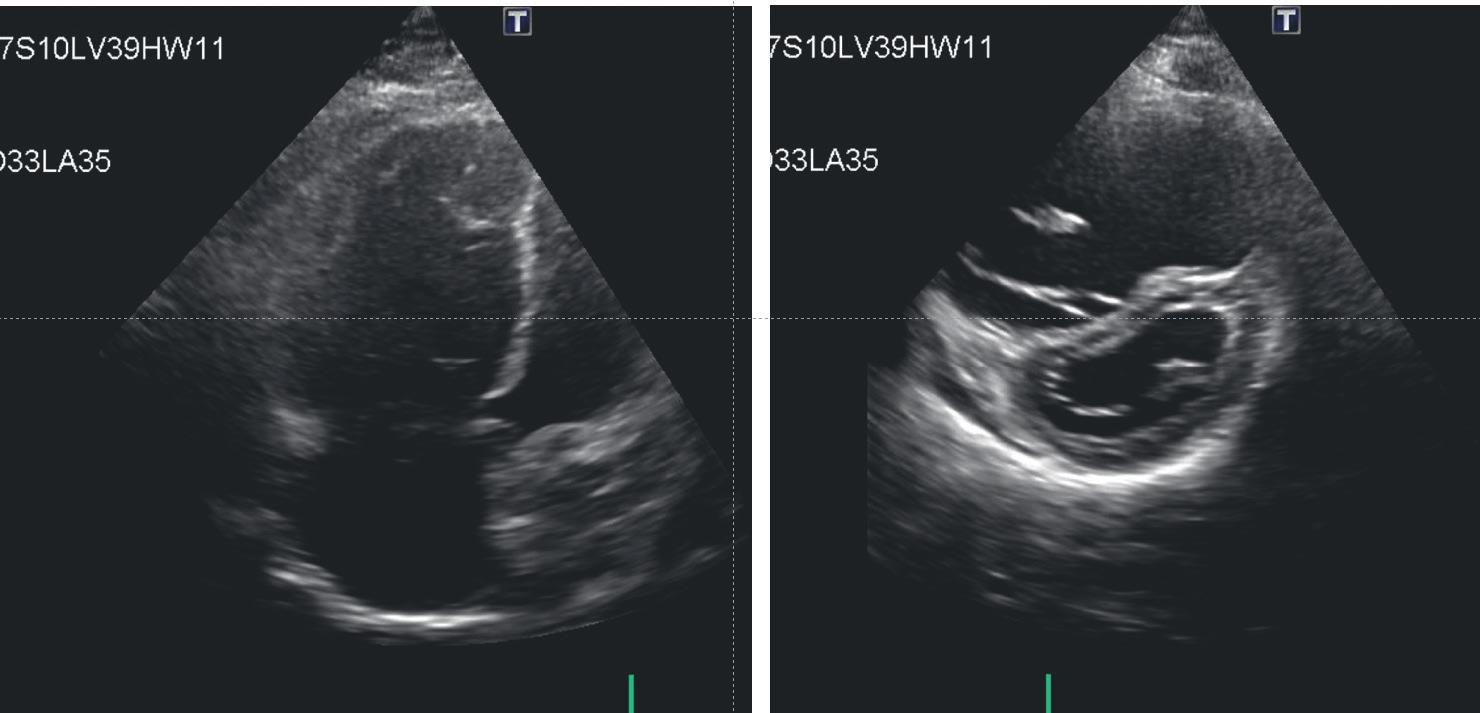

Abbildung 1: Cor pulmonale mit dilatiertem, hypertrophiertem rechtem Ventrikel, dilatiertem rechtem Vorhof. Durch die Druckbelastung kommt es zu einer D-Verformung des linken Ventrikels. Weiters zeigt sich ein minimaler Perikarderguss.

Im Lungenröntgen können sich ebenfalls Hinweise auf eine Rechtsherzbelastung finden, z. B. ein betontes Pulmonalissegment, ein verbreitertes Rechtsherz und eine Gefäßrarefizierung in der Peripherie. Mittels Echokardiographie (Abbildung 1 und 2, S. 25 & 27) können die Rechtsherzdimension und die Rechtsherzhypertrophie festgestellt werden. Anhand der Trikuspidalinsuffizienz kann der systolische PADruck ermittelt werden. Eine maximale trikuspidale Regurgitationsgeschwindigkeit TRV von über 2.8 m/s kann auf eine PH hinweisen.